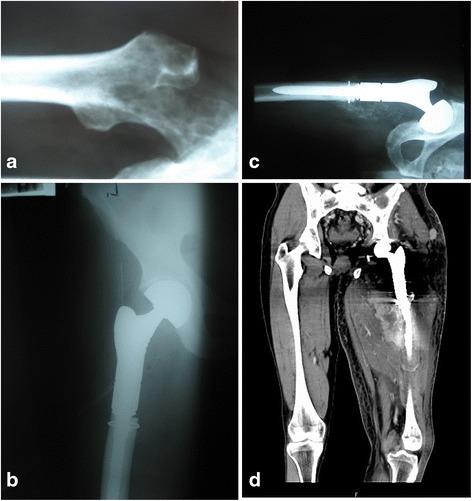

Breast, prostate, and lung cancers are the most common primary tumors that metastasize to bones. The most common site of the lesions is the proximal femur; sporadically, they do occur in bones distal to the knee and elbow. After the surgery, all the patients could walk, most of them without crutches. The pain, rated on a VAS scale, decreased significantly, and the Karnofsky score improved. We observed that joint mobility and the strength of the muscles in the limbs allowed for normal functioning. Postoperative complications including infections and local tumor recurrences were rarely observed.

乳腺癌、前列腺癌和肺癌是最常见的转移至骨骼的原发性肿瘤。最常见的病变部位是股骨近端;偶尔也会出现在膝部和肘部远端的骨骼。手术后,所有患者都能行走,大多数患者无需拐杖。根据视觉模拟评分法(VAS)评定的疼痛显著减轻,卡氏评分改善。我们观察到关节活动度和肢体肌肉力量使功能正常。很少观察到包括感染和局部肿瘤复发在内的术后并发症。